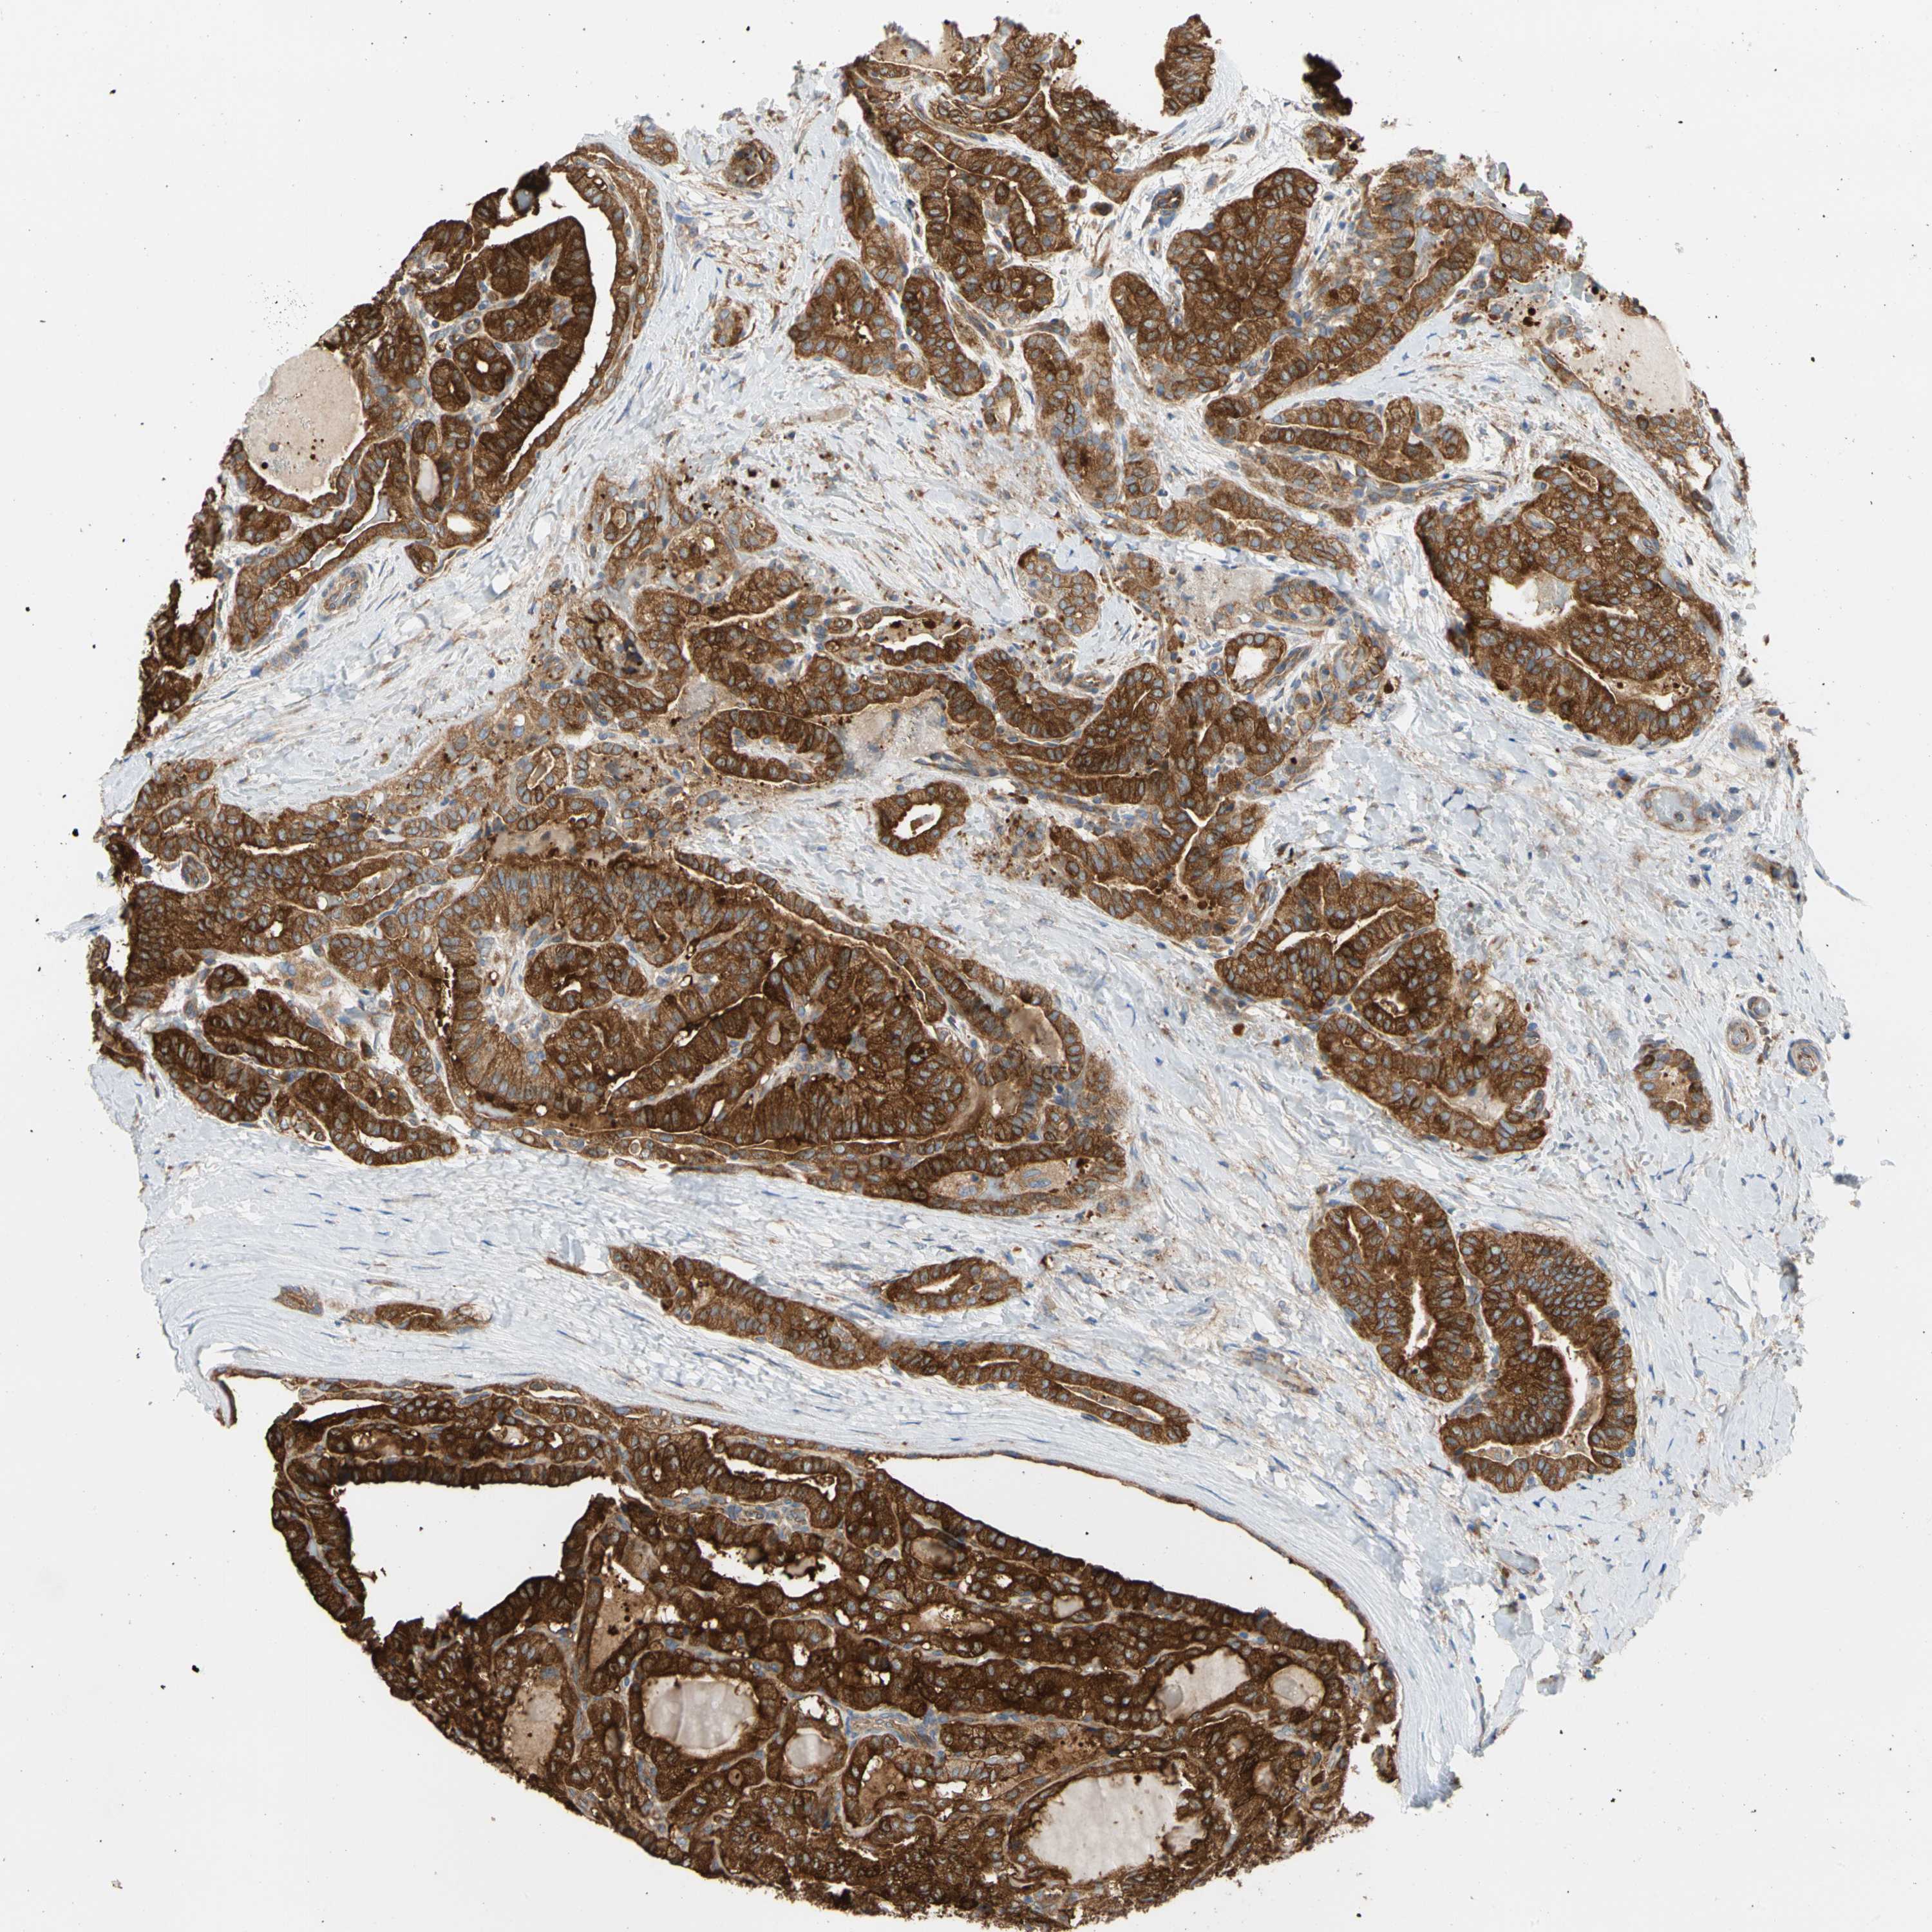

THYROID CANCER - Protein expressioni

A mouse-over function shows sample information and annotation data. Click on an image to view it in a full screen mode. Samples can be filtered based on level of antibody staining by selecting one or several of the following categories: high, medium, low and not detected. The assay and annotation is described here.

Note that samples used for immunohistochemistry by the Human Protein Atlas do not correspond to samples in the TCGA dataset.

Antibody stainingi

Antibody staining in the annotated cell types in the current human tissue is reported as not detected, low, medium, or high, based on conventional immunohistochemistry profiling in selected tissues. This score is based on the combination of the staining intensity and fraction of stained cells.

Each image is clickable and will lead to virtual microscopy that enables deeper exploration of all samples and also displays staining intensity scores, fraction scores and subcellular localization as well as patient and tissue information for each sample.

Antibody HPA003116

Antibody HPA024694

Antibody CAB004419

Staining

High

Medium

Low

Not detected

Intensity

Strong

Moderate

Weak

Negative

Quantity

>75%

75%-25%

<25%

None

Location

Nuclear

Cytoplasmic/membranous

Cytoplasmic/membranous,nuclear

Carcinoma, NOS

Follicular adenoma carcinoma, NOS

Papillary adenocarcinoma, NOS